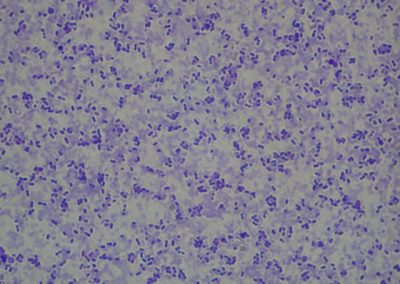

Staphylococcus spp.

Rod Staphylococcus

Rod Staphylococcus: Staphylococcus spp., kuž.